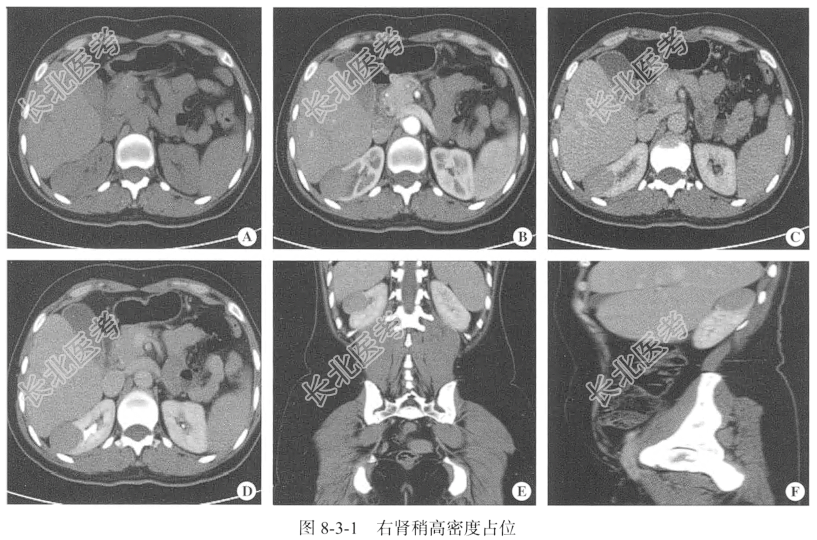

- [材料题] 【临床病史】女性,37岁。检查发现右肾占位20天。

【泌尿系统CT检查】仰卧位,横断位扫描,行泌尿系统CT平扫,冠状位、矢状位及三维重建加增强扫描(采用GE64排CT机)。增强扫描采用高压注射器经肘静脉注射非离子型碘对比剂,总量为85~90ml,流速为3.0~3.5ml/s,于注射后30秒、70~80秒、3~5分钟行皮髓质期、实质期、排泄期增强扫描。层厚5mm,层间隔5mm,螺距1。扫描范围自膈顶至髂骨翼水平。

【影像图片】见图8-3-1。

【病理所见】(右肾肿瘤)光镜下见肿瘤细胞管状、腺泡状排列,细胞形态一致,大小为5cm×3.5cm×3cm(图8-3-2)。免疫组化结果:WT1(-),CD57(+),Desmin(-),P504s(-),EMA(-),AE1/AE3(-),CK7(-),CK18(+),Vim(+)。

【病理诊断】后肾腺瘤。